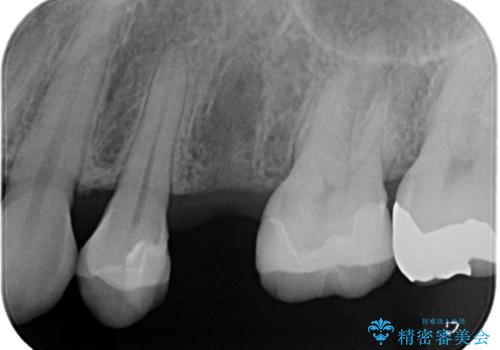

- 根管治療をしている歯が破折し、抜歯となってしまいました。

抜歯した部位に対して、はじめに可撤性部分義歯,ブリッジ、インプラントによる治療方法とそれぞれの利点と欠点について説明を行った結果、インプラント治療を希望されました。さらに、インプラント治療の術前・術後口腔内管理の重要性、手術内容,費用などを説明し、十分なインフォームド・コンセントを得たうえで治療を開始しました。

今回の症例では、骨の量が十分あったため、比較的短期間で治療を完了することができました。インプラントを使用することで、安定した咬み合わせが実現し、患者様は痛みもなく安心して食事を楽しむことができるようになりました。